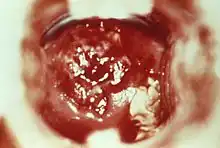

| HSV cervicitis | |

To diagnose cervicitis, a clinician will perform a pelvic exam. This exam includes a speculum exam with visual inspection of the cervix for abnormal discharge, which is usually purulent or bleeding from the cervix with little provocation.[4] Swabs can be used to collect a sample of this discharge for inspection under a microscope and/or lab testing for gonorrhea, chlamydia, and Trichomonas vaginalis. A bimanual exam in which the clinician palpates the cervix to see if there is any associated pain should be done to assess for pelvic inflammatory disease.[3]